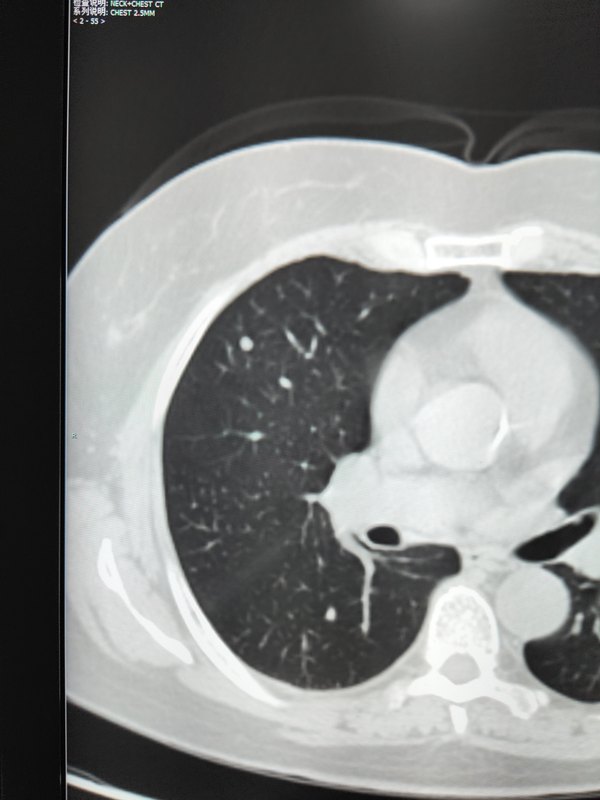

患者女性,甲狀腺癌術(shù)后,TSH>100,Tg5.2,行131碘治療,第一張圖3月份住院CT,右肺孤立肺微結(jié)節(jié)4mm;第二張圖治療后全身碘掃(遺憾的沒有斷層,本以為就是簡單的清甲治療,意外早起發(fā)現(xiàn)雙肺輕度攝碘,右上肺結(jié)節(jié)樣攝碘);第三張6月份二次碘治療CT,該結(jié)節(jié)明顯減小1-2mm,Tg1左右,綜上明確診斷肺轉(zhuǎn)移,而且碘治療效果明顯。131碘治療后全身碘掃的重要性不言而喻,該病例通過全身碘掃后早期的發(fā)現(xiàn)了肺轉(zhuǎn)移,從而進(jìn)行下一次清灶治療,相信該患者的預(yù)后也是非常好的。